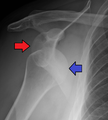

النقطة المضيئة تشير لخلع الكتف الخلفي على الجهة اليسرى. على اليمين، نفس الكتف بعد إجراء عملية الرد.

خلع الكتف الخلفي من الحالات الشائعة، وعادة ما يحدث بسبب انقباض العضلات بسبب صدمة كهربائية أو التشنج.[5] وقد يحدث نتيجة عدم توازن العضلاات المحيطة بالكتف. عادة ما يحمل المريض ذراعه بصورة دائرية إلى الداخل، كما تضعف العضلات المحيطة بالكتف مع حالة إصابة واضحة في النتوء الغرابي.

قد يحدث الخلع الخلفي لأسباب غير معروفة، وخاصة بين كبار السن[11] وفي حالات الصدمة الغير واعية.[12] في دراسة لمجموعة من 40 حالة، لوحظ أن الفترة بين الإصابة والتشخيص تصل إلى عام.[13]